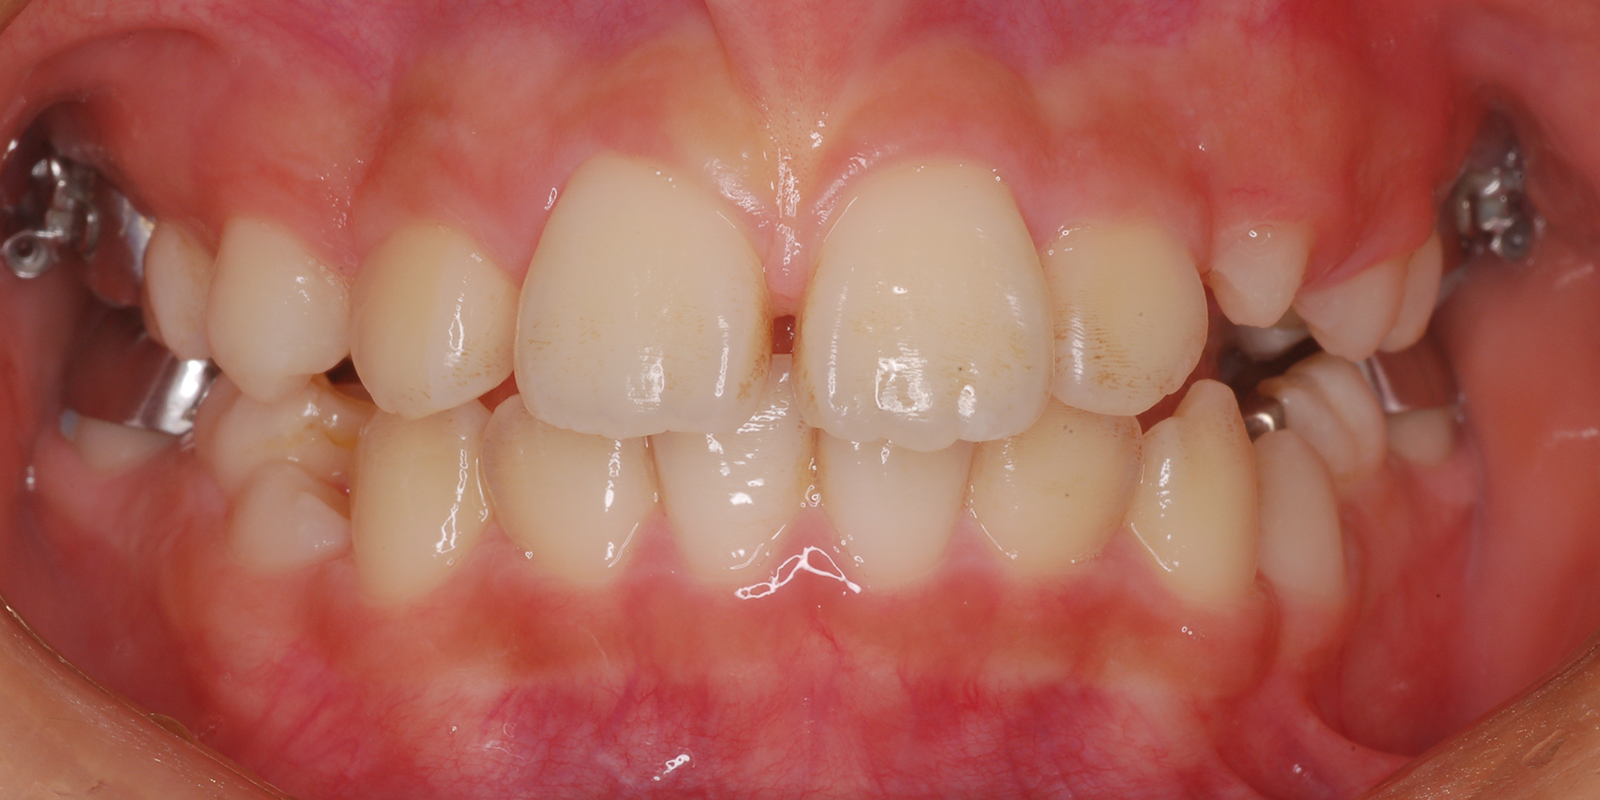

術前

| 主訴 | 叢生 |

| 診断 | アングルⅡ級1類 |

| 初診時年齢 | 9歳10か月 |

| 装置 | ヘッドギアー(1期治療) 若干上顎が大きく、大臼歯関係が上顎大臼歯が前に出て上顎前突のため、上顎大臼歯を遠心に送るためヘッドギアーを使用しました。 |

| 抜歯・非抜歯 | 上下左右第1小臼歯を抜歯、マルチブラケット(2期治療) 大臼歯関係が正しい関係になりましたが、叢生、歯軸の関係が悪いので、永久歯の抜歯を行いました。 |

| 治療期間 | 1期治療:1年10ヶ月 2期治療:3年 |

| 通院回数 | 1期治療:13回 2期治療:約36回 |

| 治療費 | 約100万円 矯正歯科治療は公的医療保険の適用外の自費(自由)診療となります |

| 治療のリスク | ・装置を使用しなければ効果が出ない ・歯に痛みが出ることがある ・取り外しのため、なくすことがある ・ブラッシングが悪い場合虫歯や歯肉炎になります |